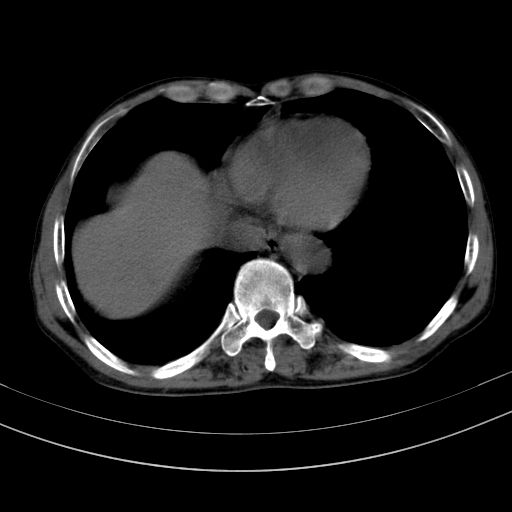

以下是引用37度在2010-1-9 14:37:00的发言:[br]1.双肾囊肿,左肾积水结石,.胆总管轻度扩张;[br]2.病灶在腹膜外,考虑纤维瘤。

以下是引用dyqct在2010-1-9 17:56:00的发言:[br]考虑:1.双肾囊肿,左肾积水结石、旋转不良。[br] 2.右侧腹直肌血肿或纤维瘤。[br]肠道准备不好。做个增强。